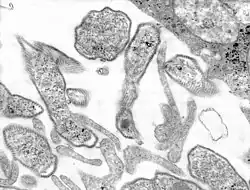

Mumpsvirus in der TEM-Abbildung | ||||||||||||||||||||||

Das Virion des Mumpsvirus erscheint rund bis unregelmäßig mit einem mittleren Durchmesser von 150 nm. In der Virushülle befinden sich zwei Hüllproteine (F1 und F2), von denen das F1 eine Hämagglutinin- und Neuraminidase-Aktivität aufweist. F1 und F2 lagern sich als Heterodimer zusammen und bilden das so aktive Fusionsprotein zum Eintritt in die Zelle. Die Innenseite der Hülle ist von einem Matrixprotein bedeckt, das den Zusammenbau des Viruspartikels beim Austritt an der Zellmembran ermöglicht.